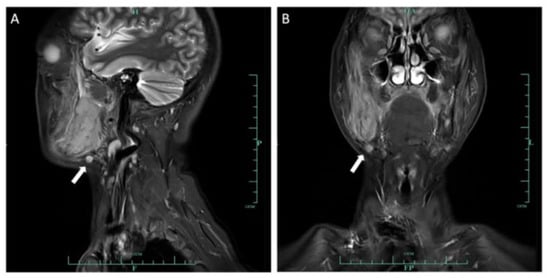

2.2. Case 2